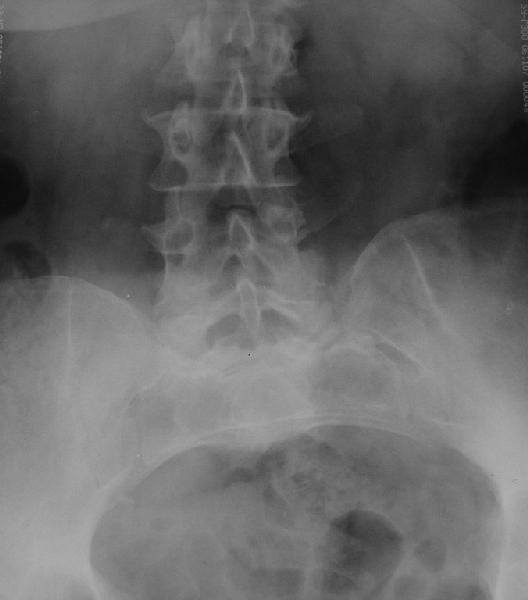

У больной 53 лет в последний год появились сильные боли в пояснице.

При обследовании выявлен анкилоз тазобедренного сустава в приведении. Видимо, в период пребывания в тяжелом состоянии появились гетеротопические оссификаты. За исключением того, что осталась одна почка, сейчас других медицинских проблем нет.

Крайне желательно выполнить МРТ поясничного отдела, так как на представленных рентгенограммах складывается впечатление о спондилолистезе L5,котрый наиболее вероятно и является причной болевого синдрома. Кроме того у болной имеется высокий риск гнойного поражения позвоночника. Только после МРТ можно планировать коррекцию вторичной деформации позвоночника.

Снимок поясничного отдела плохо просматривается на моем компе. Нет ли там спондилолистеза L5-S1?

После корригирующей остеотомии сохранится чрезмерная нагрузка на поясничный отдел за счёт анкилоза т/бедр. сустава.На фоне остеохондроза,спондилёза,спондилоартроза и спондилолистеза устранение порочного положения не избавит от болей и вряд-ли даже уменьшит их.Мне кажется тут нет альтернативы эндопротезированию.Но даже в этом случае не исключено,что позднее, на повестке появится необходимость вмешательства на позвоночнике.

Учитывая отсутствие жалоб со стороны тазобедренного сустава - оперативое лечение вряд ли принесет позитивный результат. На первый план выступает спондилолизный спондилолистез (вниматльно посмотрите снимки поясничного отдела)L5 позвонка. На наш взляд больному рекомндовано выполнить транспедикулярную коррекцию и фиксацию сегментов L4-S1 с установкой кейджа в L5-S1.